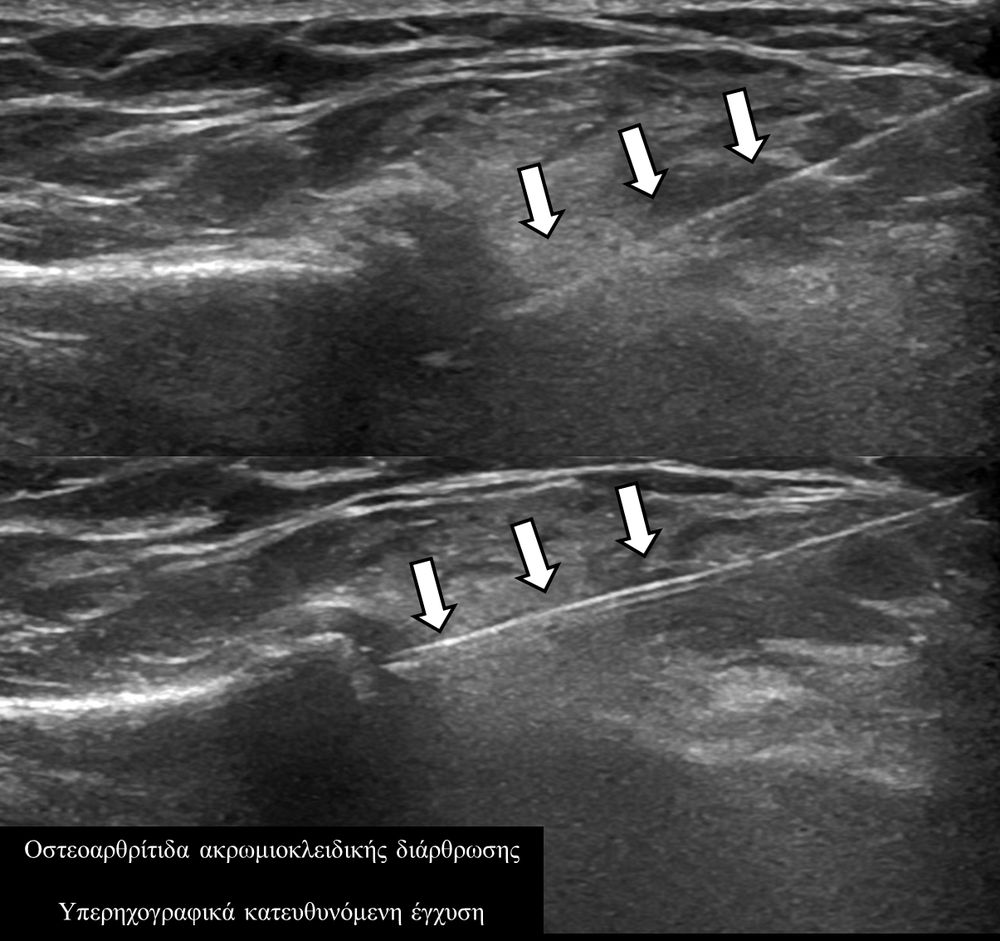

Υπό συνεχή υπερηχογραφική παρακολούθηση είναι δυνατόν να πραγματοποιηθούν κατευθυνόμενες εγχύσεις σε ορθοπαιδικές και ρευματολογικές παθήσεις. Αρχικά εντοπίζεται η παθολογική περιοχή και στη συνέχεια εξετάζεται η βέλτιστη οδός προσπέλασης. Ακολούθως γίνεται υπό άμεση και συνεχή υπερηχογραφική παρακολούθηση οι απαραίτητοι χειρισμοί και έγχυση φαρμάκων ακριβώς στη θέση της βλάβης.

Εχει αποδειχθεί ότι με την υπερηχογραφική καθοδήγηση εξασφαλίζεται:

- μεγαλύτερη ακρίβεια και αποτελεσματικότητα (αφού η έγχυση/θεραπεία γίνεται ακριβώς στηνπαθολογική περιοχή)

- καλύτερη ανοχή από τον ασθενή (λιγότεροι τραυματικοί χειρισμοί αφού έχουμε άμεση και συνεχή εποπτεία της βελόνας)

- μεγαλύτερη ασφάλεια (αποφυγή τρώσης νεύρων, αγγείων, γειτονικών ανατομικών δομών).

- ενδοαρθρικά(πχ οστεοαρθρίτιδα)